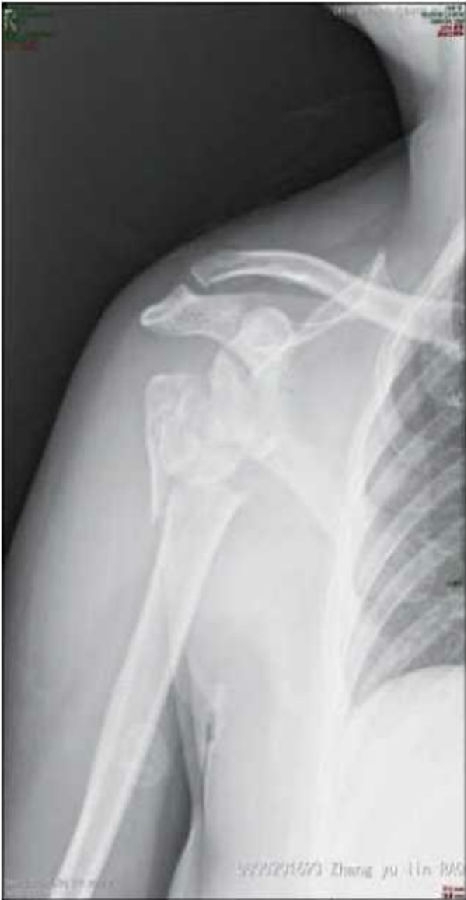

该例患者为65岁肱骨近端骨折术后患者,肩关节功能严重受损(图11~13)。

图11 肩关节X线片示肱骨近端骨折术后肱骨大、小结节吸收